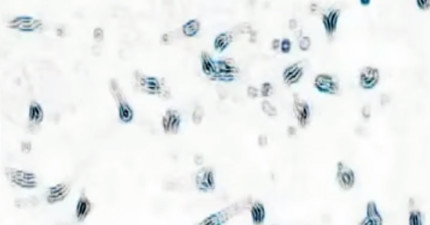

這就是將大麻注入癌細胞後會發生的醫學奇蹟!